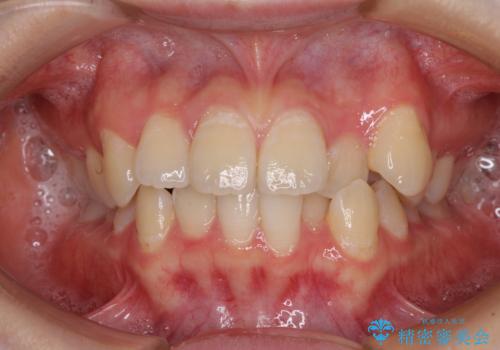

【モニター】左右のクロスバイトをインビザラインできれいに改善